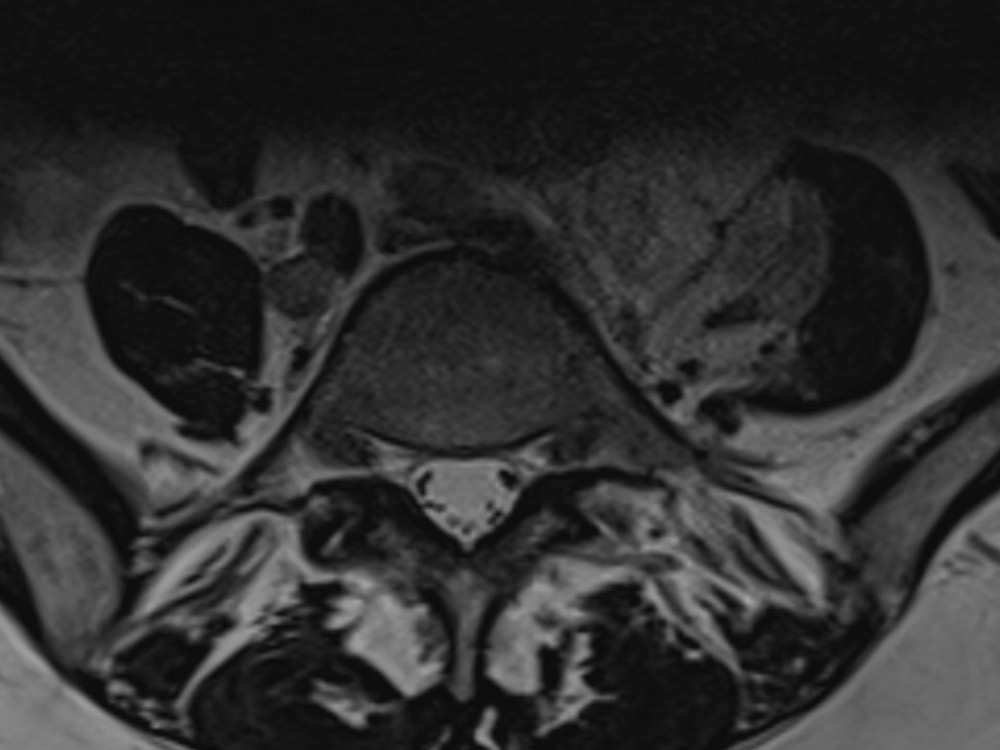

E. Dion 06/11/2019